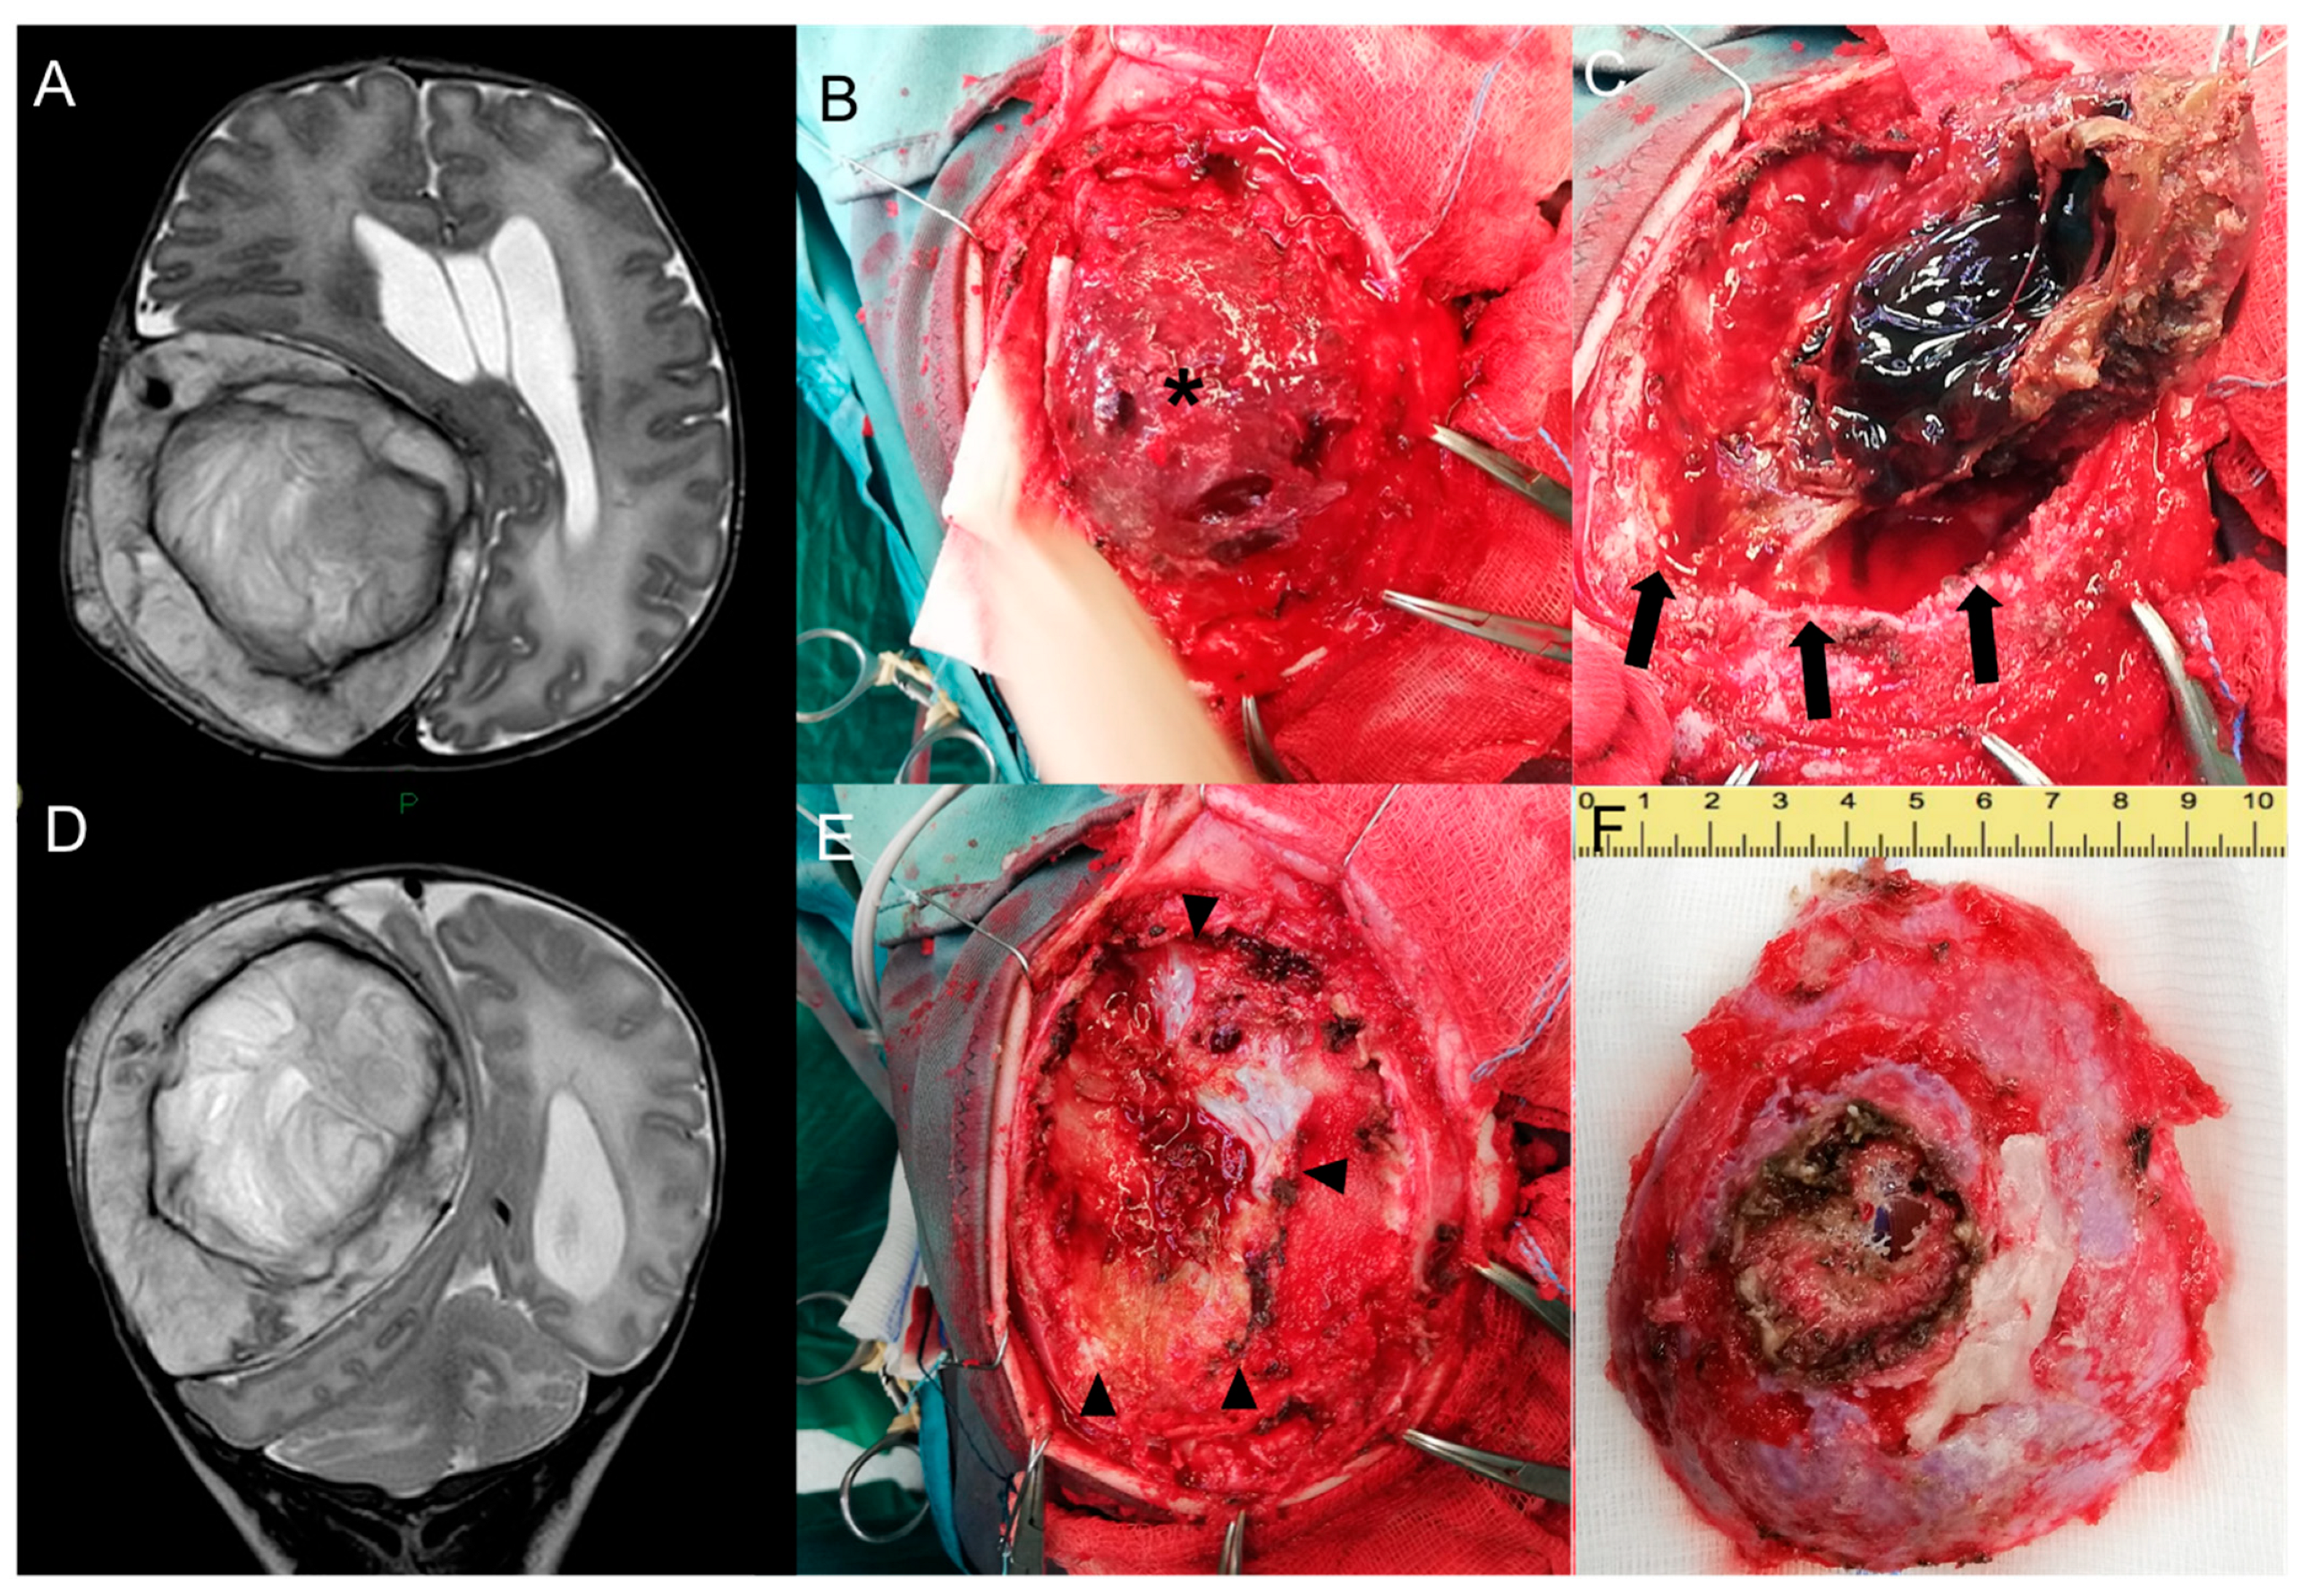

2.2. Endovascular Embolization and Surgical Treatment